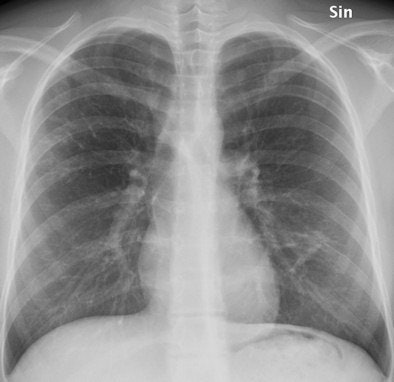

The anteroposterior (AP) chest x-ray, which is automatically included in the examination, shows increased linear markings in the right upper lobe and small parenchymal changes in the left lung, lateral to the heart. All images courtesy of Dr. Kristina Vult von Steyern.

The anteroposterior (AP) chest x-ray, which is automatically included in the examination, shows increased linear markings in the right upper lobe and small parenchymal changes in the left lung, lateral to the heart. All images courtesy of Dr. Kristina Vult von Steyern.In an article published online on 11 November by Insights into Imaging, Dr. Kristina Vult von Steyern, a pediatric radiologist at Skäne University Hospital's Center for Medical Imaging and Physiology in Lund, Sweden, and colleagues described their experiences using digital tomosynthesis imaging with a patient population of 39 adults ages 19 to 59 years and 36 children ages 8 to 18 years. All were participants of a clinical study of cystic fibrosis patients.